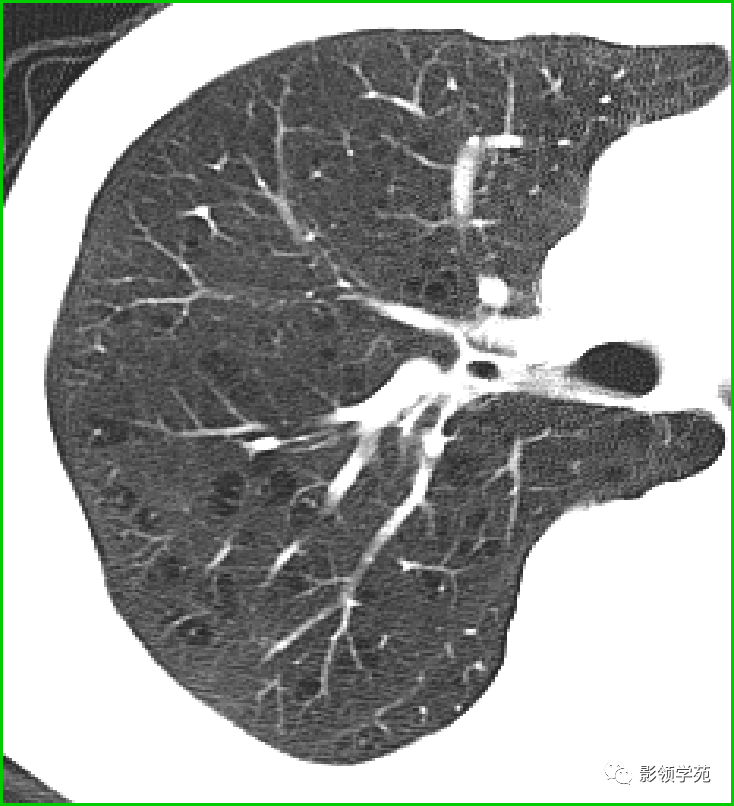

过敏性肺炎

马赛克征